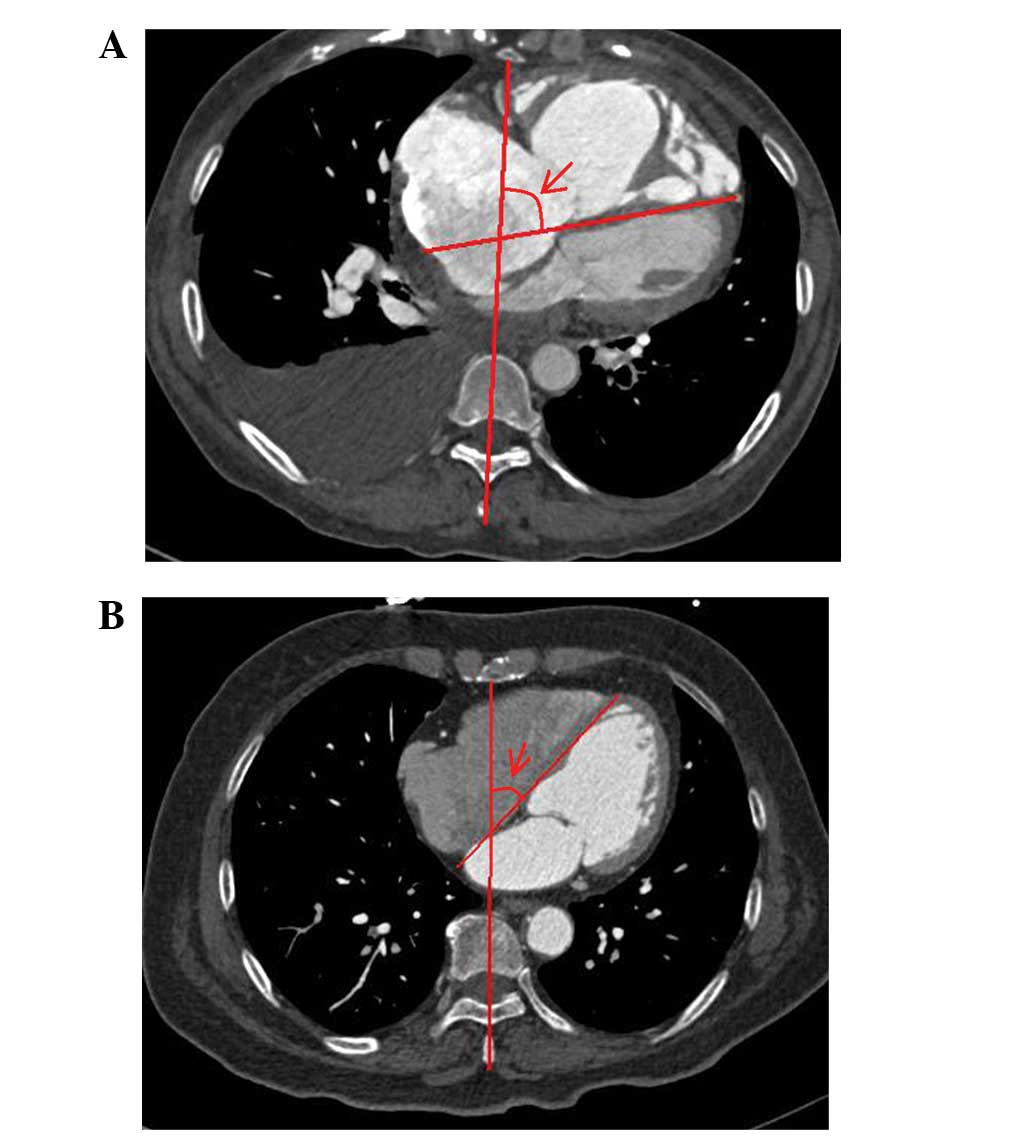

Non-invasive evaluation of hemodynamics in pulmonary hypertension by a Septal angle measured by computed tomography pulmonary angiography: Comparison with right‑heart catheterization and association with N-terminal pro-B-type natriuretic peptide

The septal angle, an angle between the interventricular septum and the line connecting the sternum midpoint and thoracic vertebral spinous process, as measured by computed tomographic pulmonary angiography (CTPA), has been observed to be increased in patients with pulmonary hypertension (PH), but its meaning remains unclear. The aim of this study was to investigate the potential role of the septal angle in evaluating hemodynamics and its association with N-terminal pro-B-type natriuretic peptide (NT-proBNP) in patients with PH. Patients with PH (n=106), including 76 with chronic thromboembolic pulmonary hypertension (CTEPH) and 30 with pulmonary artery hypertension (PAH), were retrospectively reviewed. The patients underwent CTPA prior to right-heart catheterization. The septal angle was measured on transversal CTPA images. Hemodynamic parameters were evaluated by right-heart catheterization. The level of plasma NT-proBNP was measured by enzyme‑linked sandwich immunoassay. The septal angle had a moderate correlation with cardiac output (CO; r=-0.535, P=0.000) and a high correlation with pulmonary vascular resistance (PVR; r=0.642, P=0.000). The mean level of NT-proBNP in PH was 1,716.09±1,498.30 pg/ml, which correlated with the septal angle (r=0.693, P=0.000). In a stepwise forward regression analysis, the Septal angle was entered into the final equation for predicting PVR, leading to the following equation: PVR = 28.256 x Septal angle - 728.72. In CTEPH, the Septal angle strongly correlated with NT-proBNP (r=0.668, P=0.000) and PVR (r=0.676, P=0.000). In PAH, the Septal angle strongly correlated with NT-proBNP (r=0.616, P=0.003) and PVR (r=0.623, P=0.000). The CTPA‑derived Septal angle is a superior predictor for evaluating and monitoring the level of NT-proBNP and PVR in patients with PH.